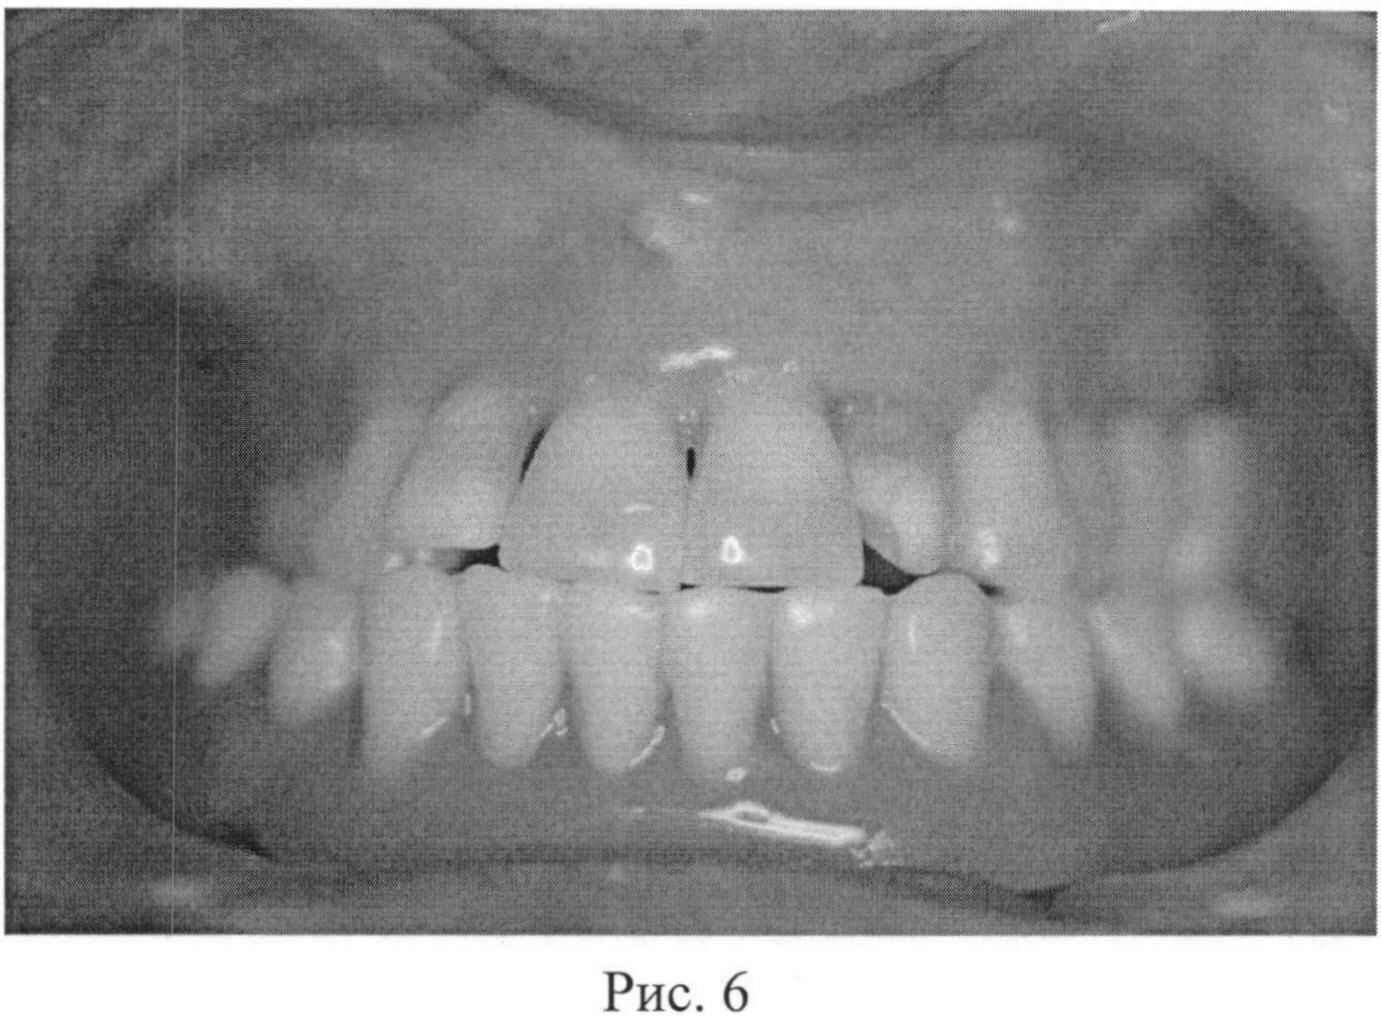

После остеоинтеграции имплантатов, через 4 месяца пациентка была направлена в ортопедическое отделение, где была изготовлена ортопедическая конструкция с опорой на дентальные имплантаты (рис. 6).

[31]